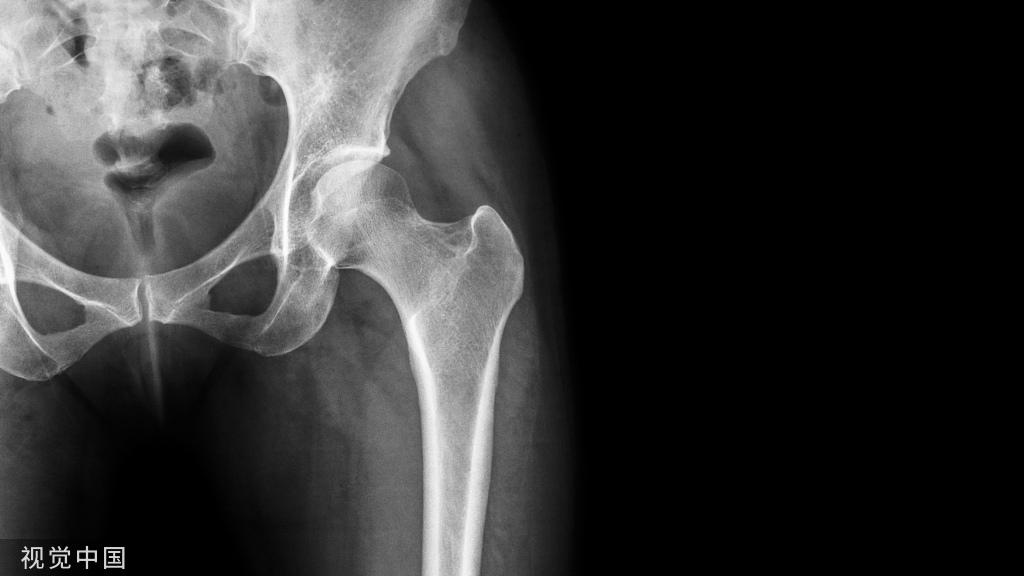

2023年中华医学会显微外科学分会第十一届委员会成立,在全面推进健康中国战略的背景下,显微外科学也迎来新的发展机遇。多学科交融、智能化发展、复杂疾病的精准治疗成为显微外科学发展和创新的新突破。笔者对2023年度显微外科重要进展进行简要回顾,希望读者对我国显微外科学发展有更多的了解。一、显微外科手术机器人——智能与精细化的新突破在光学显微镜对血管、神经、淋巴管等组织放大后,显微外科手术医生需要进行毫米至微米尺度的缝合手术。在操作过程中不精细的手部动作会损伤吻合组织或者造成吻合口不通,导致手术失败。相比于人的肌肉,机器人有着更高的精度和稳定度。目前,Maastricht University的研究人员在新型机器人系统——MUSA的辅助下完成了一项淋巴管吻合的手术实验。这是首次在机器人辅助下完成的“超显微外科手术”。研究表明MUSA具有更高的操作精度,外科医生移动操纵杆1 cm,机械臂移动精度可达0.1 mm,可辅助完成直径范围为0.3~0.8 mm的血管及淋巴管的吻合。目前,解放军联勤保障部队第九二〇医院与上海微创公司合作,参考中国的数字人解剖数据,与智能化数字解剖相结合,正在研发显微外科手术机器人,已进行多项实验。未来通过结构设计的优化,可进一步提高显微外科手术机器人的定位精确性和输出力,将人手的较大动作转化为机器人的微小精细动作,可以极大地提高手术过程的精度,从而真正把显微外科手术机器人推向临床应用,也必将成为我国显微外科智能与精细化的新突破。█ 二、游离皮瓣移植与3D打印微孔钛(钽)假体结合开启修复重建新思路皮瓣外科与新材料的结合是显微外科领域近年来的一大热点,能大大减少手术难度,并加快术后康复。解放军联勤保障部队第九二〇医院徐永清团队率先开展的游离皮瓣结合3D打印微孔钛(钽)假体研究,为缺损骨组织打印出解剖形态完全相同的微孔钛(钽)假体,结合显微外科皮瓣技术,为每一个复合组织缺损的创面制定精确化、个性化的修复重建方案。该项技术目前临床应用21例,成功率为90.4%,避免了传统治疗方案存在的治疗周期较长、患者依从性差、骨组织短缺等问题。南方医科大学南方医院任高宏、王剑利团队利用该项技术成功应用于多项肢体复杂的复合组织缺损的病例,也为各级医院诊治下肢软组织伴随大段骨缺损提供了良好的范例。三、颈7神经移位术——重塑大脑功能治疗中枢性上肢偏瘫的新应用中枢性偏瘫是指因脑卒中、脑外伤、脑瘫等中枢神经损伤造成的肢体偏瘫,既往多采用康复功能锻炼,对于偏瘫较重的患者效果不理想。复旦大学附属华山医院徐文东团队在发现“一侧大脑具有控制双侧上肢的潜能”后,带领团队进行了大量研究。颈7神经既有支配上肢感觉的功能,又有支配上肢运动的功能,切取一侧的颈7神经,对健侧肢体的运动和感觉功能不会受到太大影响。根据此原理,团队利用显微外科技术,将健侧颈7神经移位至瘫痪侧的颈7神经,避开损伤的大脑半球,完成八个点的对位吻合,使偏瘫上肢与同侧健康大脑半球连接。在神经移位后,大脑半球的功能成功重塑,通过术后的康复锻炼,促使一侧健康大脑实现对双侧上肢的控制。四、脊髓T1神经根切断术——治疗上肢的痉挛性瘫痪的新途径多源性脑损伤(脑外伤、脑卒中、脑瘫等)导致的肢体痉挛性瘫痪严重影响个体的独立生活能力,给社会和家庭造成沉重负担。国内外相关研究表明,外周神经部分切断联合系统的康复辅助治疗,对痉挛性上肢瘫的肩、肘、腕关节功能改善有效,但临床上一直找不到缓解手屈曲痉挛稳定有效的方法,而手屈曲痉挛的解除是改善手功能的关键点之一。经过十多年的潜心研究以及临床病例的积累,北京积水潭医院王树锋、李文军团队从功能解剖上分析,发现当大脑皮质广泛损伤后,脊髓T1节段前角γ运动神经元的兴奋性反应性增强,T1神经根切断后可以持久、有效地缓解中枢性手屈曲痉挛。这一新技术的发明为此类患者手功能改善提供了新途径和新思路,是显微外科治疗上肢痉挛性瘫痪的又一新手段,也得到了国家重点研发计划“主动健康和人口老龄化应对专项”的立项与资助。五、淋巴结组织瓣移植治疗淋巴水肿的新发现淋巴结组织瓣移植手术是将患者身体中健康的淋巴结组织移植到淋巴水肿部位,以促进淋巴液的流动和排出。传统动静脉淋巴结组织瓣移植治疗淋巴水肿已于临床应用30余年,是淋巴外科主流治疗方法之一。然而,同时具备动静脉供养的淋巴结组织瓣供区较少,仍然是限制此方法应用和推广的重要因素。上海交通大学医学院附属第九人民医院章一新团队探究了静脉淋巴结组织瓣治疗淋巴水肿的潜力,并依据供血方式不同,将静脉淋巴结组织瓣进行分型研究。此研究结果将为淋巴结组织瓣移植提供更多的静脉淋巴结供区,并为临床应用静脉淋巴结组织瓣移植治疗淋巴水肿解除更多的限制,有利于该手术的应用和推广。六、世界首例新生儿的同种异体上肢移植在我国获得成功同种异体肢体移植是指将一个人体的一部分肢体(如手臂、腿等)移植到另一个人的身体中。同种异体肢体移植需要进行严格的配型和免疫抑制治疗,以避免移植物被宿主免疫系统攻击而失败,其术后的长期生存率不高。山东省立医院王增涛团队开展了世界首例新生儿同种异体上肢移植获得成功。该病例为一对早产新生儿双胞胎,在出生2个月后,哥哥因左上肢“束带综合征”导致手臂坏死,而弟弟因多器官衰竭失去了生命。孩子父母提出把弟弟的上肢移植给哥哥的想法。这一想法经过王增涛团队与医院各科室的反复讨论及多方会诊,制定了从术前准备、麻醉、手术、术后护理与康复的周密的围手术期方案,成功实施了新生儿同种异体上肢移植术。目前该患儿移植的左上肢感觉与运动功能从肩关节到肘关节再到手指正在一步步地恢复,该病例为世界首例新生儿同种异体上肢移植,为同种异体移植开创了新篇章。 七、全手脱套伤显微外科治疗的新思路全手脱套伤创面与功能的修复重建是显微外科领域一个巨大挑战,往往因手术方案和技术限制导致术后功能丧失,甚至截肢的发生。宁波市第六医院收治了一名全手脱套伤的年轻患者,该患者右手被滚筒碾压,整个右手的皮肤自远侧腕横纹水平脱套缺损,深部组织除大小鱼际肌和手内肌有部分损伤,指骨和肌腱相对完整。王欣教授带领8名医生采用分组团队合作的方式,游离移植7块组织瓣一期为患者再造全手,并同时显微修复双侧供足缺损。具体术式如下:①用胸背动脉穿支皮瓣修复右手掌、手背皮肤缺损;②用双足带足背皮瓣的第1、第2趾甲皮瓣再造右手1-4指;③用双侧股前外侧穿支皮瓣修复双足供区创面。目前患者右手外观、感觉和活动功能均恢复良好,能够完成吃饭、穿衣、拿钥匙开门、抓捏小物体、开车、捏握车把手等动作,而且双足皮瓣质地良好,双足外观满意,不影响穿鞋,能正常走路和跑步,且步态与常人无异。全手脱套伤的治疗是国际公认的难点,王欣教授不仅再造了脱套的全手,而且应用穿支皮瓣技术修复了双足供区,使再造手在获得良好外观和功能的同时,也显著降低了足部供区的病损,充分体现了“供、受区并重”的修复理念,为全手脱套伤的治疗提供了新思路。